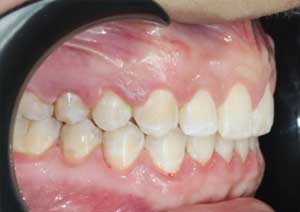

Le traitement de la supraclusion : Le traitement de la supraclusion repose avant tout sur un diagnostic précis, permettant de déterminer son origine dento-alvéolaire, squelettique ou mixte, ainsi que l’âge du patient.

Les objectifs principaux sont de réduire le recouvrement incisif, de rétablir une dimension verticale équilibrée et d’assurer une fonction occlusale stable.

Après